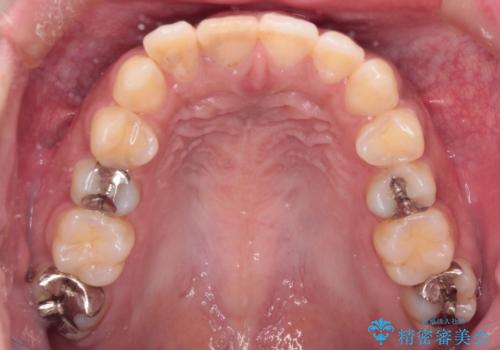

前歯の突出感を改善|上下4本の抜歯と審美ワイヤー矯正でバランスの取れた口元へ

- 患者様は、前歯の突出感を気にされて来院されました。診察の結果、歯列のスペースが不足しており、前歯を後方へ移動させるには抜歯が必要と判断。上下の小臼歯4本を抜歯し、目立ちにくい審美ワイヤー矯正(白いワイヤーと透明ブラケット)を使用して治療を行う計画を立てました。

抜歯によって前歯を下げるためのスペースを確保。その後、審美ワイヤー矯正を用いて、歯列全体のバランスを整えながら前歯を後方へ移動させました。治療後は、横顔のラインが整い、自然な口元になったことで、見た目も噛み合わせも改善しました。患者様からは「口元がすっきりして、自信を持って笑えるようになった」と喜びの声をいただきました。